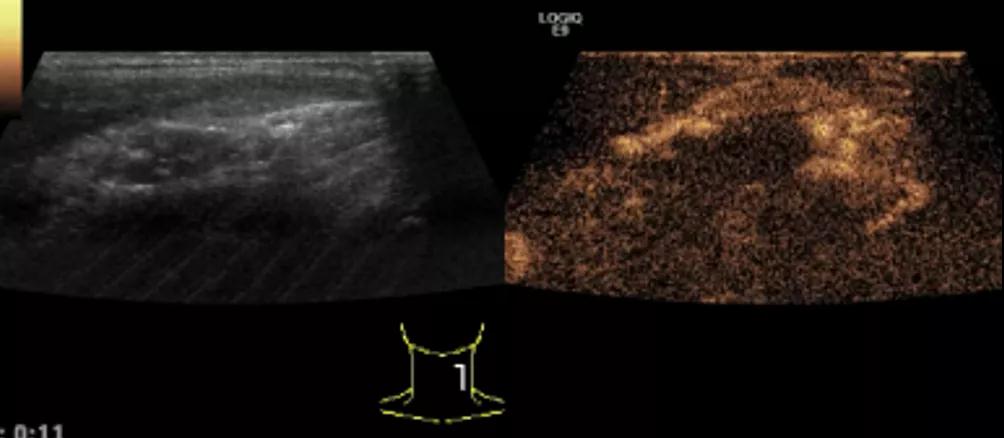

第5例是乳腺癌的患者,右乳恶性肿瘤术后化疗后1年出现淋巴结转移,患者基本情况差,拒绝放化疗,行局部热消融后也实现充盈缺损,术后一个月强化信号消失。

(病例5图例)